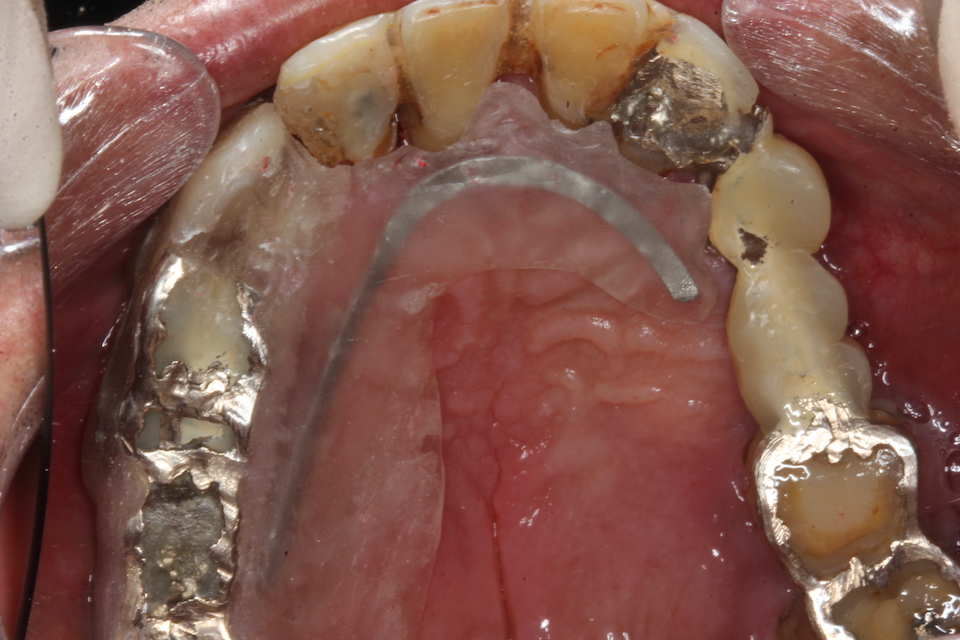

パッチン義歯2.1(削らないブリッジ) 2025.11.04

半口腔内製作義歯1.0 2025.06.24

半口腔内製作義歯0.6 2025.06.17